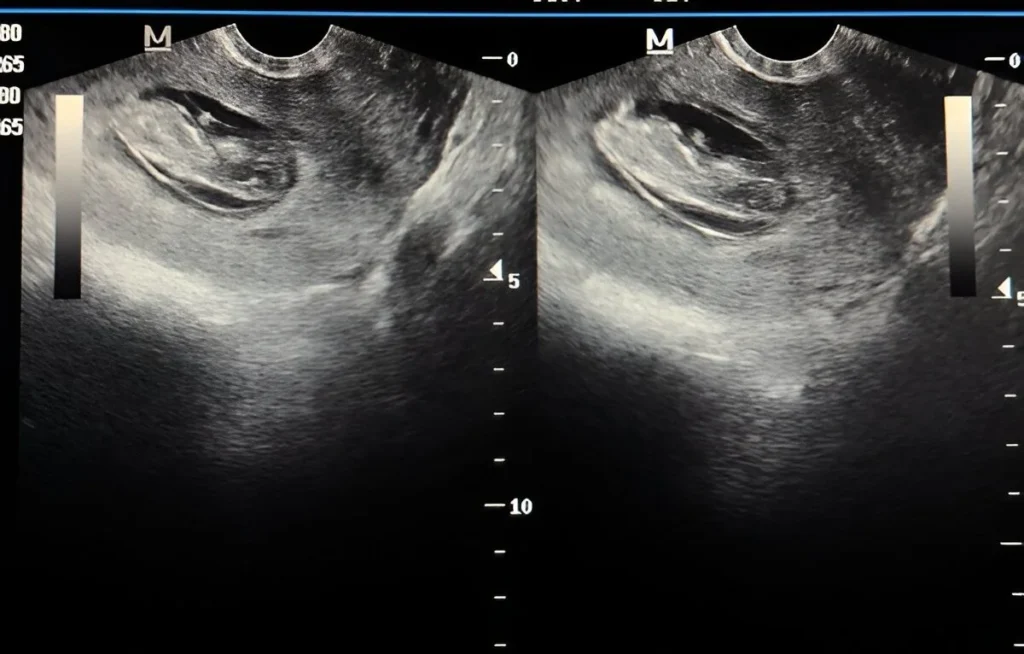

Early Ultrasound for Dating (6–10 weeks)

• Confirms pregnancy viability

• Determines gestational age

• Detects early concerns like subchorionic bleed, twins, etc.

Transvaginal Sonography (TVS)

High-resolution imaging for early pregnancy, placental location, cervix length, previa, and targeted evaluations.